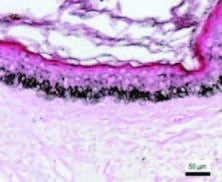

- Dieser Dermisbereich mit flacher DEJ ist die Zieltiefe für die Mikronadel. Siehe Pfeile, wo die Mikrokanäle gebildet werden

EPIDERMALE MELANINDICHTE BEI MELASMA VOR DEM EINGRIFF